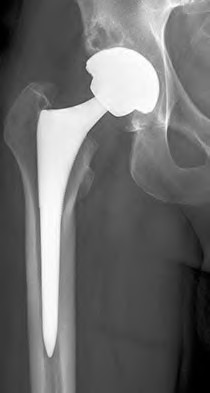

ORTHOPEDIC MCQS ONLINE OB 20 1D RECONSTRUCTION A 77-year-old man who had right total knee replacement surgery…